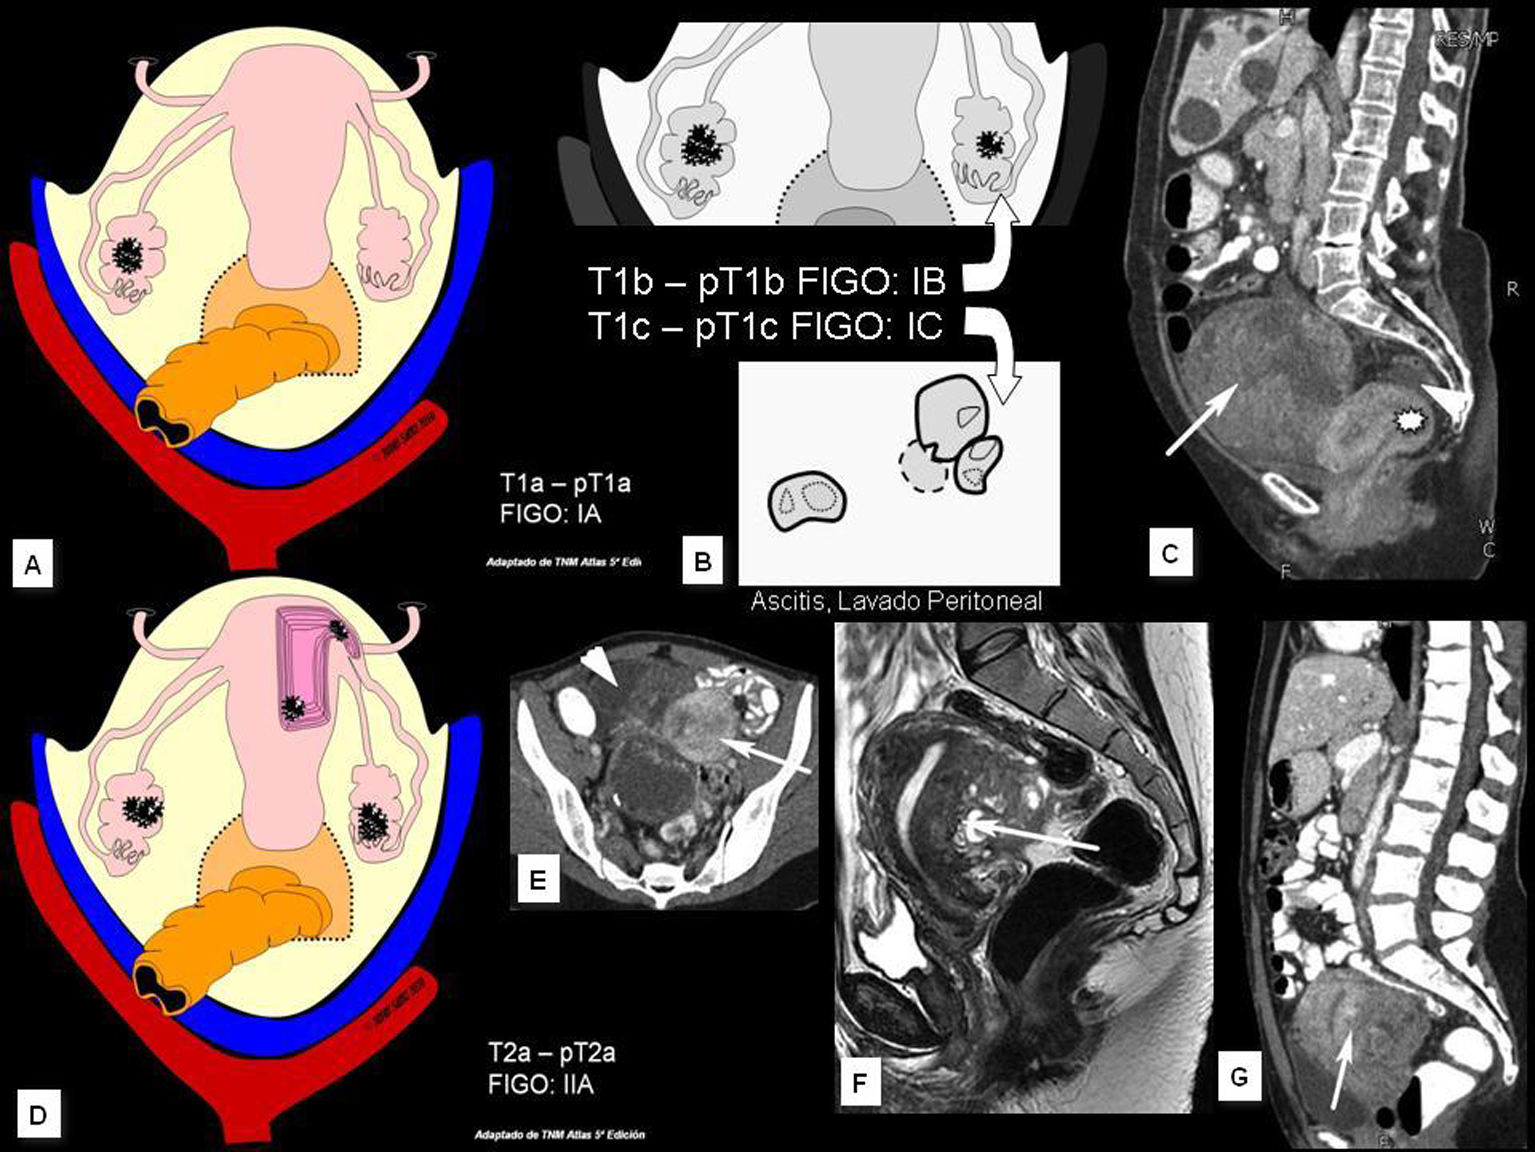

En el contexto del abordaje multidisciplinar para el diagnóstico y tratamiento del cáncer de ovario, la aportación del radiólogo incluye cuatro puntos fundamentales que son: identificación de la lesión, caracterización, estudio de extensión y valoración evolutiva. En el presente trabajo se describen los hallazgos y claves diagnósticas en TCMD (Tomografía Computarizada multidetector) y RM (Resonancia Magnética), la aportación e indicación de otras tecnologías como el PET (Tomografía por Emisión de Positrones) y se esbozan las técnicas emergentes basadas en imagen funcional (estudios dinámicos con contraste en RM y estudios de difusión por RM).Descargas